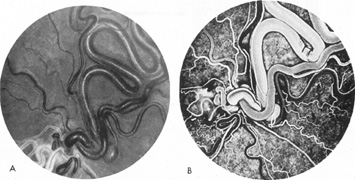

Vertebrobasilar System

Tortuous or redundant basilar arteries are not uncommon in the older age group. Occasionally, gross dilation or ectasia develops so that the basilar artery acts as a mass in the posterior fossa. This phenomenon produces signs of low-pressure hydrocephalus, cranial nerve palsies, and long tract and sensory signs and may even simulate a cerebellopontine angle tumor or tumor at the foramen magnum.58 It is possible to diagnose such lesions with CT59 or MRI60 but angiography is definitive (Fig. 6). The association of insidious multiple cranial nerve palsies and long tract signs referable to a brainstem level, in an elderly patient with evidence of atherosclerosis, should make fusiform basilar artery dilation a diagnostic consideration.

Fig. 6. Fusiform basilar dilation. A: Lateral projection vertebral arteriogram showing a widened basilar artery (arrow) projecting beyond level of dorsum sellae. B: Anteroposterior projection showing a widened and tortuous basilar artery.